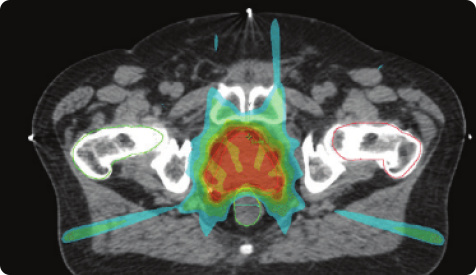

前列腺疾病防治&康复:​1.智能早期诊断体系2.微创手术诊疗体系3.前列腺术后快速康复管理4.前列腺微创手术尿控功能恢复体系5.前列腺微创手术性功能保护体系